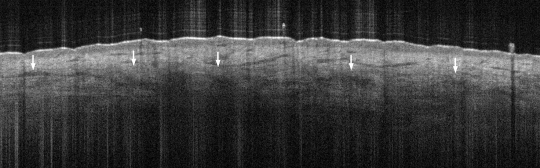

Reticular Dermis Lowest visible layer of follicular skin Hyporeflective mottled texture due to hyperreflective collagen bundles and a high fluid content from tissue fluid perfusion and vessels Leave a comment Cancel reply You must be logged in to post a comment.